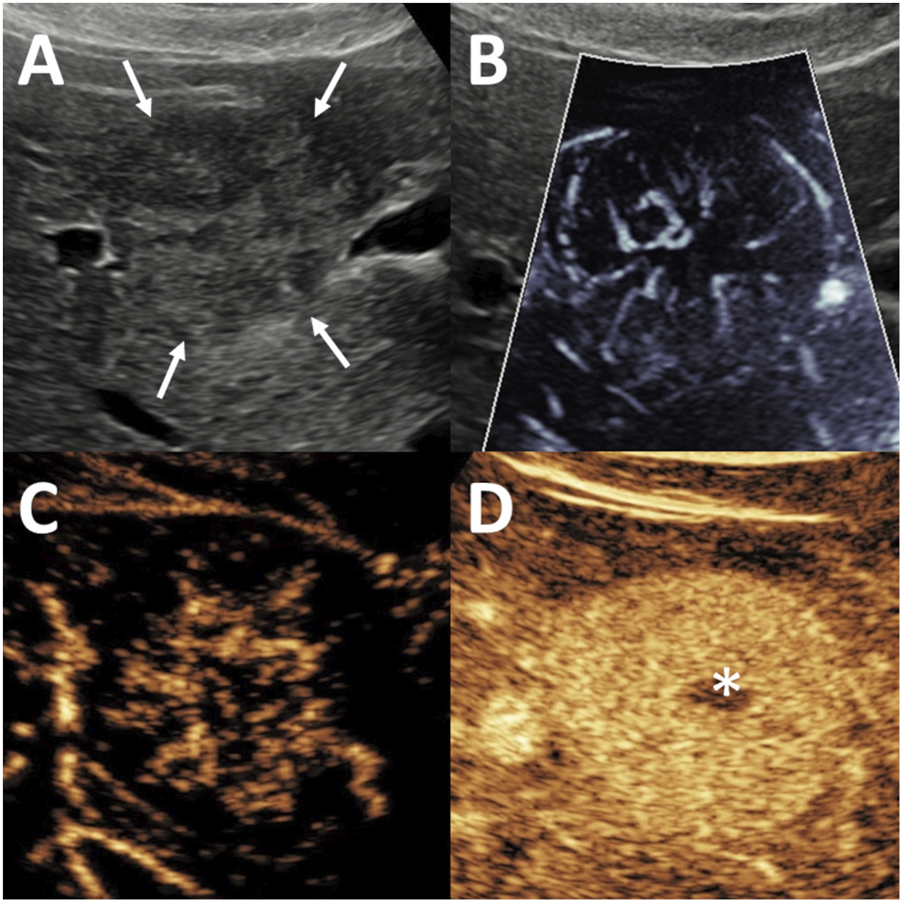

FIGURE 2

Evaluation of focal nodular hyperplasia (FNH) using microvascular imaging (MVFI) and contrast-enhanced ultrasound (CEUS). The lesion, measuring 20 mm in diameter, was located in segment 5, right beneath the liver capsule. (A) B-mode ultrasound (US) shows a nearly isoechoic lesion with poorly defined margins (arrows). (B) MVFI reveals a characteristic spoke-wheel vascular pattern. (C) In the early arterial phase of CEUS, the lesion demonstrates centrifugal enhancement with stellate vascularity. (D) During the venous phase, the lesion remains hyperenhancing relative to the surrounding liver, and a centrally located hypoenhancing scar (asterisk) is visible.

Common MVFI patterns detected in FNH

The spoke-wheel vascular pattern was the characteristic MVFI feature of FNH. It was identified in 35 FNH lesions (85%) by the first observer and in 26 lesions (88%) by the second observer (Figure 2). A non-specific hypervascular pattern was observed in 4 FNHs (10%) by the first observer and in 3 FNHs (7%) by the second. Alternative MVFI patterns, including spotted-dot, nodular rim with central dot, and basket-wave configurations, were each observed in only one FNH lesion (2%) by either observer. Among FNH lesions measuring <3 cm, the spoke-wheel pattern was detected in 12 cases (80%) by both observers. The spoke-wheel pattern was highly specific for FNH, as indicated by the observations of the first (OR = 51.53; 95% CI: 16.68–191.51; p < 0.001) and second observer (OR = 35.28; 95% CI: 12.00–124.65; p < 0.001).

However, spoke-wheel-like appearances were occasionally identified in non-FNH lesions: the first observer noted this pattern in 3 HCCs (14%), 2 HCAs (20%), and 1 MET (5%), the second observer in 4 HCCs (19%), 3 HCAs (30%), and 3 METs (15%).

The presence of a central artery on MVFI was found to be a characteristic feature of FNH according to the first observer (OR = 4.96; 95% CI: 1.19–23.00; p < 0.03), but this association was not statistically significant for the second observer (OR = 1.85; 95% CI: 0.45–7.10; p = 0.373). The first observer identified a central artery in 30 FNH lesions (73%), as well as in 4 HCCs (19%), 3 METs (15%), and 2 HCAs (20%) (Figure 3). In comparison, the second observer detected a central artery in 32 FNHs (78%), 8 HCCs (38%), 6 METs (30%), and 3 HCAs (30%).